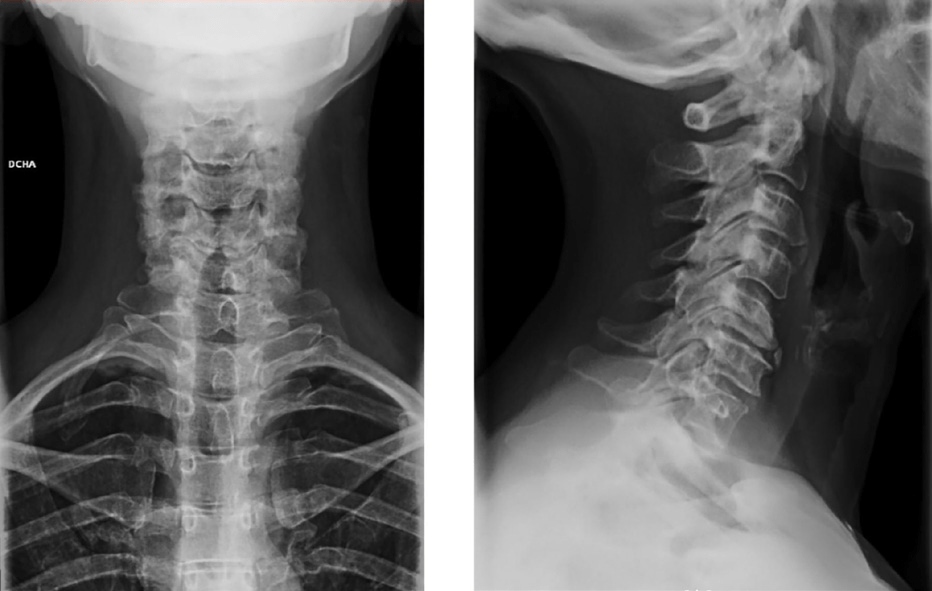

- Rx: rectificación de lordosis cervical. Cambios degenerativos en segmento C5-C6 con disminución de espacio en dicho nivel.

- RMN: discopatía cervical grave C4-C7, especialmente crítica en C5-C6 sin alteraciones de señal medular.